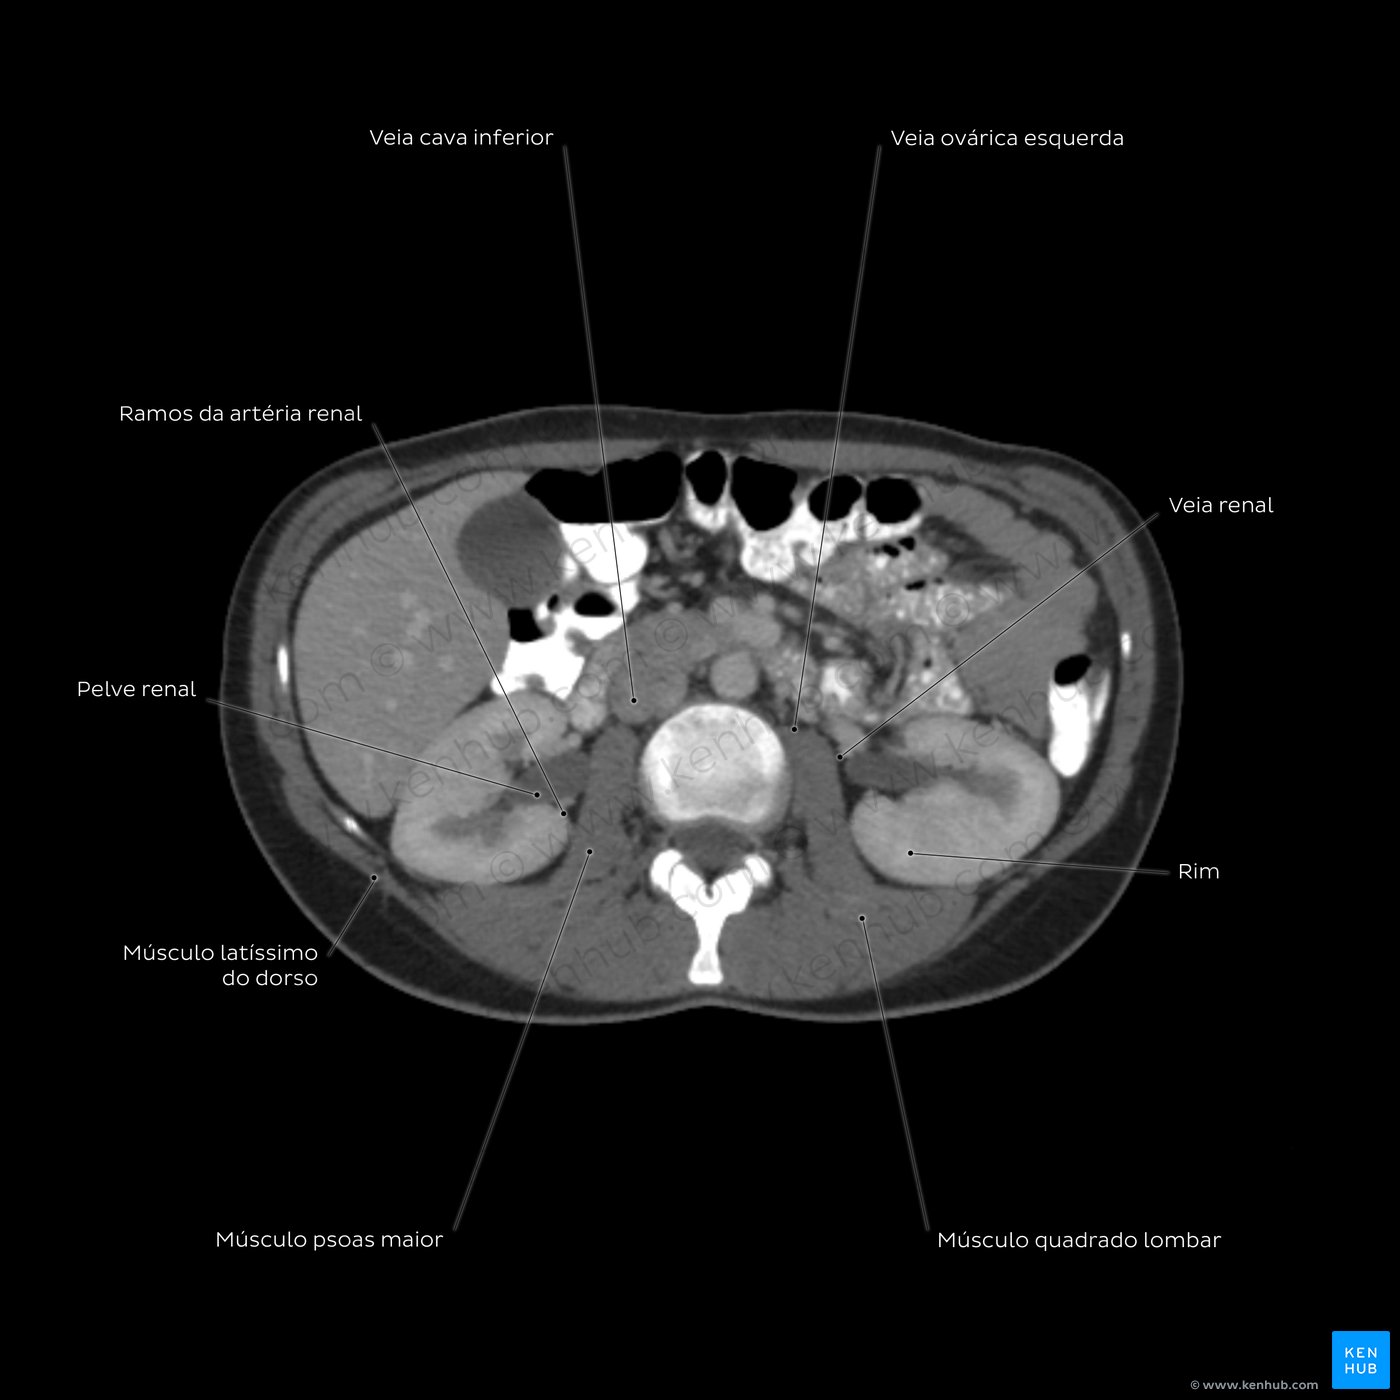

Esquema de TC abdominal ao nível de L3

Vamos começar com o anel externo em cinza, ele representa a pele. Movendo internamente, nós vemos a camada escura de tecido subcutâneo. A próxima camada de tecido cinza é a representação dos músculos do tronco. Anteriormente você deve ser capaz de identificar os músculos abdominais: reto abdominal, oblíquos externo e interno e transverso do abdômen. Posteriormente, nós temos os músculos do dorso: latíssimo do dorso, eretores da espinha, quadrado lombar e iliopsoas. Entre os músculos posteriores está a vértebra L3, branca (hiperdensa). Seu corpo vertebral é separado do arco posterior pelo canal vertebral, em cinza.

Os órgãos abdominais estão situados internamente aos músculos. Vamos começar com os órgãos sólidos. Você pode ver claramente o fígado, ele é cinza e preenche a maior parte do espaço direito do paciente. Ligeiramente mais hipodensa e implantada na porção anterior do fígado, está a vesícula biliar. Em seguida, vejamos o pâncreas, este órgão é cinza médio e está localizado centralmente na nossa imagem tomográfica. Movendo posteriormente, note os órgãos pareados, idênticos nos lados esquerdo e direito, estes são os rins. Note como a pelve renal é mais escura que o parênquima renal. Agora vamos ver os órgãos ocos, ou seja, o estômago e intestinos delgado e grosso. Eles estão preenchidos por ar e, por isso, seus lúmens estão pretos. Centralmente na imagem, podemos ver os círculos cinzas dos grandes vasos. Procure na imagem a veia cava inferior, a aorta abdominal, bem como a artéria renal e sua veia correspondente.